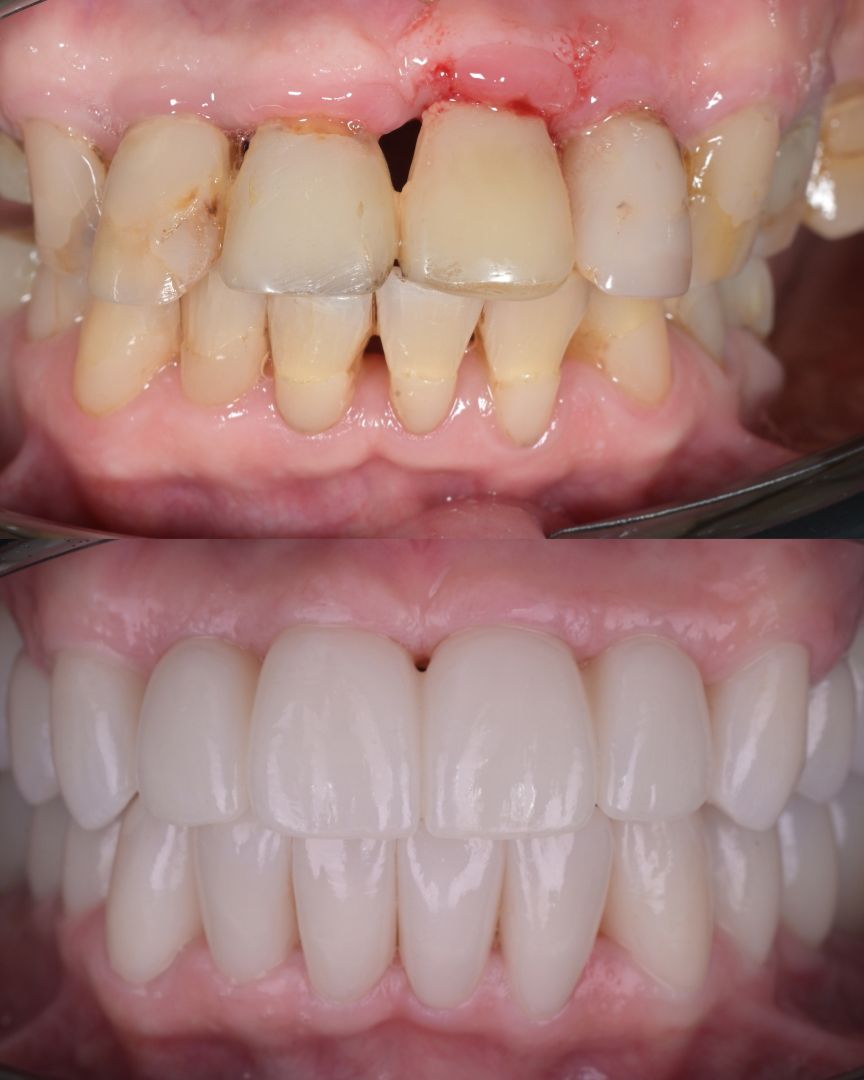

до и после